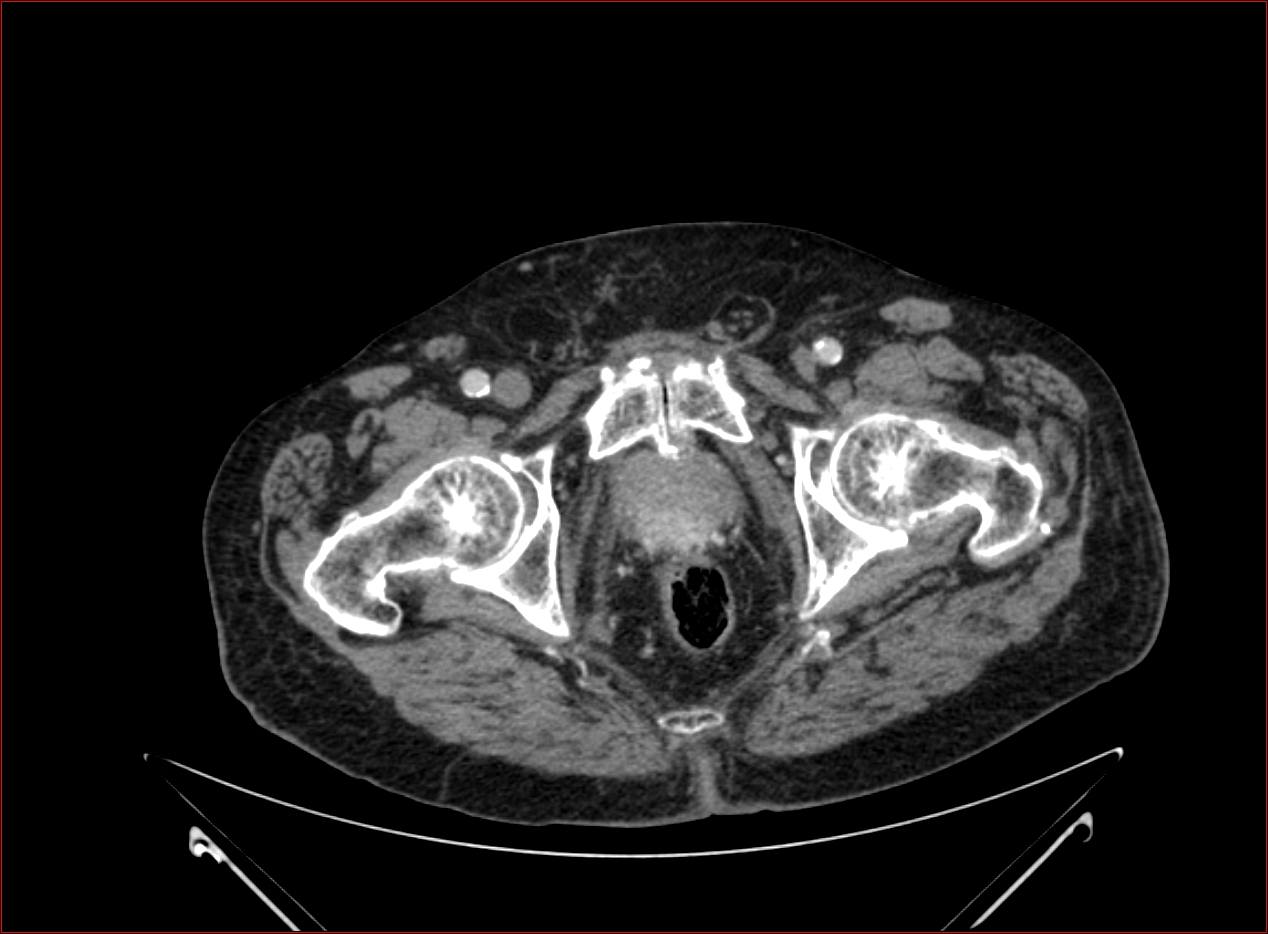

Prostata carcinoma (CT) Szerző: admin | júl 7, 2010 | Prostata | Nincsenek hozzászólások erintett a rectum elulso fala beszurt a holyag is kismedencei megnagyobbodott nyirokcsomo